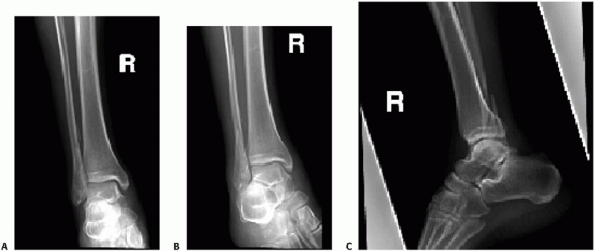

![]() |

FIGURE 57-2 Example of standard ankle trauma series including AP (A), mortise (B), and lateral (C).

anteroposterior (AP), 15-degree internal rotation AP (mortise), and

lateral views (Fig. 57-2). Using these three

views is best for ensuring that the diagnosis of fracture instability

is made; however, AP and lateral views only can be sufficient and may

provide a great deal of information regarding the integrity of the

ankle.26 To manage the large volume